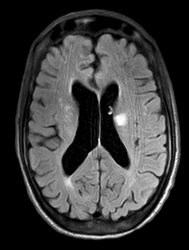

Approximately 50% of patients with GPA have neurologic symptoms, most commonly headache or mononeuritis multiplex. Approximately 10% of patients will have imaging evidence of small-vessel vasculitis in the brain or spinal cord, which may lead to ischemic strokes, hemorrhage, or white matter lesions on MRI, as were seen in our patient. Liver involvement is also common and portends a poorer prognosis, as does the absence of sinus symptoms. In contrast, the absence of renal disease is associated with better outcomes. Treatment usually consists of glucocorticoids combined with rituximab or cyclophosphamide. In the setting of rapidly progressive renal failure or severe alveolar hemorrhage, plasma exchange may be useful (GPA granulomatosis with polyangitis treatment with steroid and cyclophosphamide).